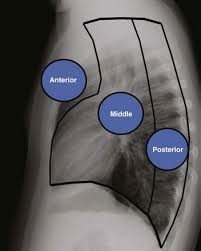

Kəskin mediastinit əksər hallarda ikincili xəstəlikdir, başqa sözlə, döş qəfəsi və ya ətraf orqanlarda baş verən zədələnmə və ya irinli iltihabi xəstəliklərin ağırlaşmasıdır (Şəkil 8).

- Ətraf orqanlarda baş verən irinli iltihabın divararalığına keçməsi nəticəsində baş verən mediastinitlərə də az rast gəlinmir. Plevra və ağciyərin xəstəlikləri (irinli plevrit, abses), boyun, retroperitoneal fleqmona, qabırğaların, fəqərələrin, döş sümüyünün osteomielitləri divararalığına yayıla bilər.

Kəskin mediastinitin diaqnozunu dəqiqləşdimək üçün ən vacib müayinə KT-dir. KT-də divararalığında ödem, maye, hava, kontrast ekstravazasiyası mediastinitin xarakterik əlamətləridir.